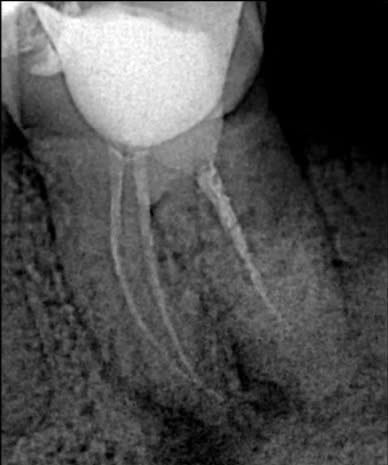

1) до перепломбировки; |